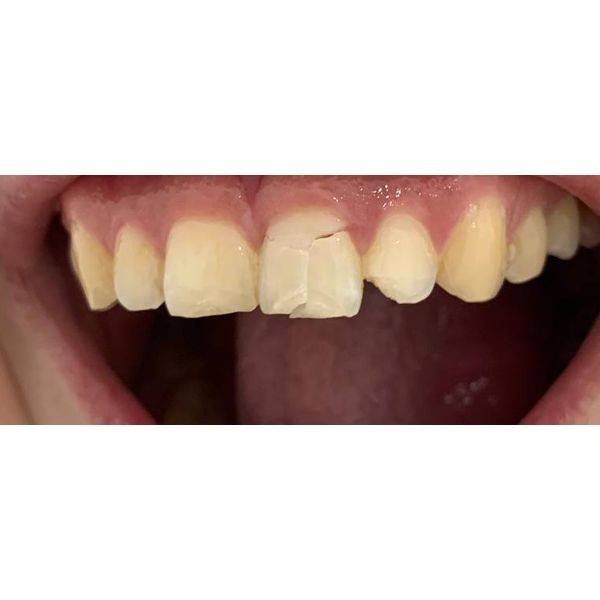

Слизистая полости рта бледно-розовая, умеренно увлажнённая, рот открывался полностью, кожа чистая, региональные лимфатические узлы не прощупывались (норма). Отсутствовал 21-й зуб, наблюдались сколы режущего края передних зубов (11, 12 и 22).

11, 12 и 22 зубы раньше не лечили, у них были сколоты режущие края без вскрытия пульповой камеры.